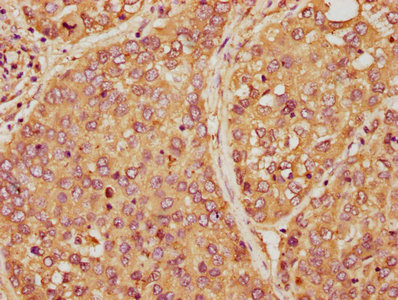

应用范围:ELISA, WB, IHC

推荐稀释比:

Application Recommended Dilution WB 1:500-1:5000 IHC 1:20-1:200 -